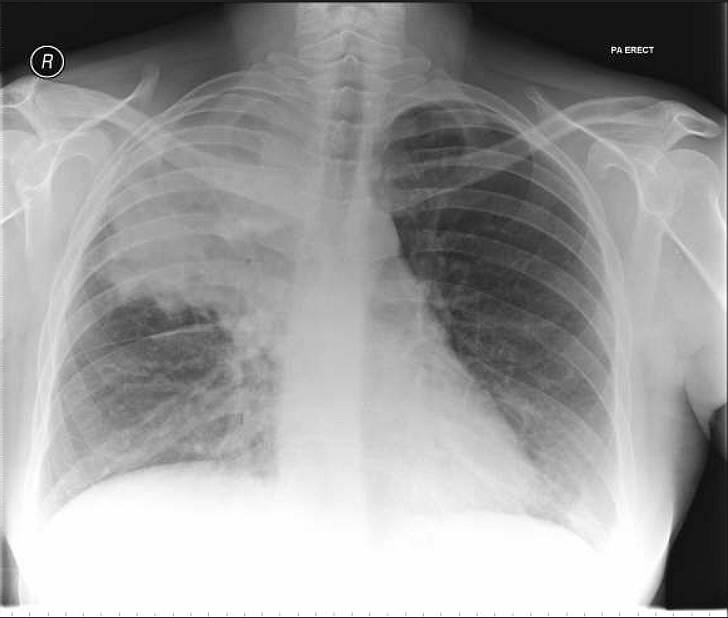

This 35-year-old lady in the 24th week of gestation presented with a 2 day history of pleuritic chest pain and dyspnoea. On clinical examination she was apyrexial but tachypnoeic with no crackles on auscultation.

The following day she became acutely unwell, pyrexial and on chest auscultation right sided crackles were elicited. A chest x-ray was requested. Her past medical history included two previous pulmonary emboli for which she was receiving dalteparin throughout her pregnancy.

What’s the diagnosis ?